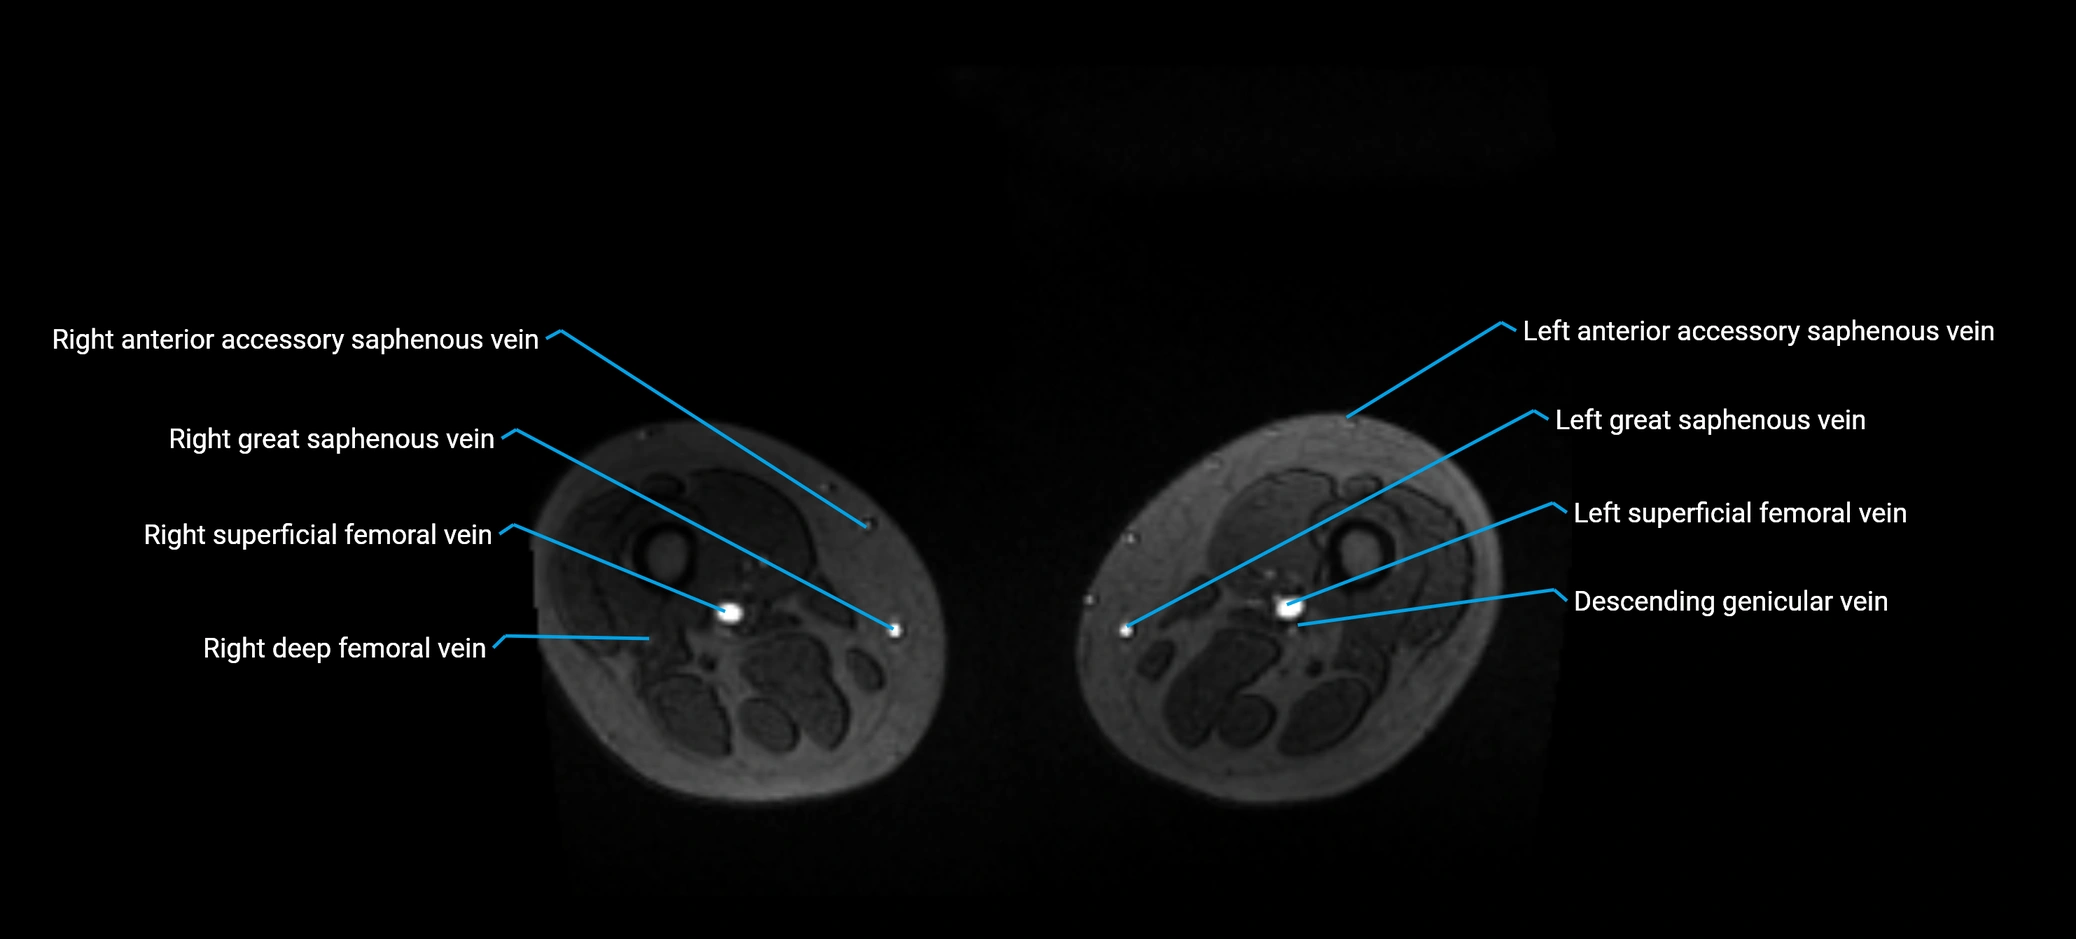

MRI image

image